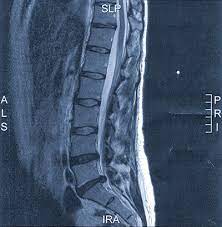

Mrt Bild Lendenwirbelsaule Bandscheibe Hat Jemand Ahnung Gesundheit Und Medizin Ruckenschmerzen Bandscheibenvorfall Lws